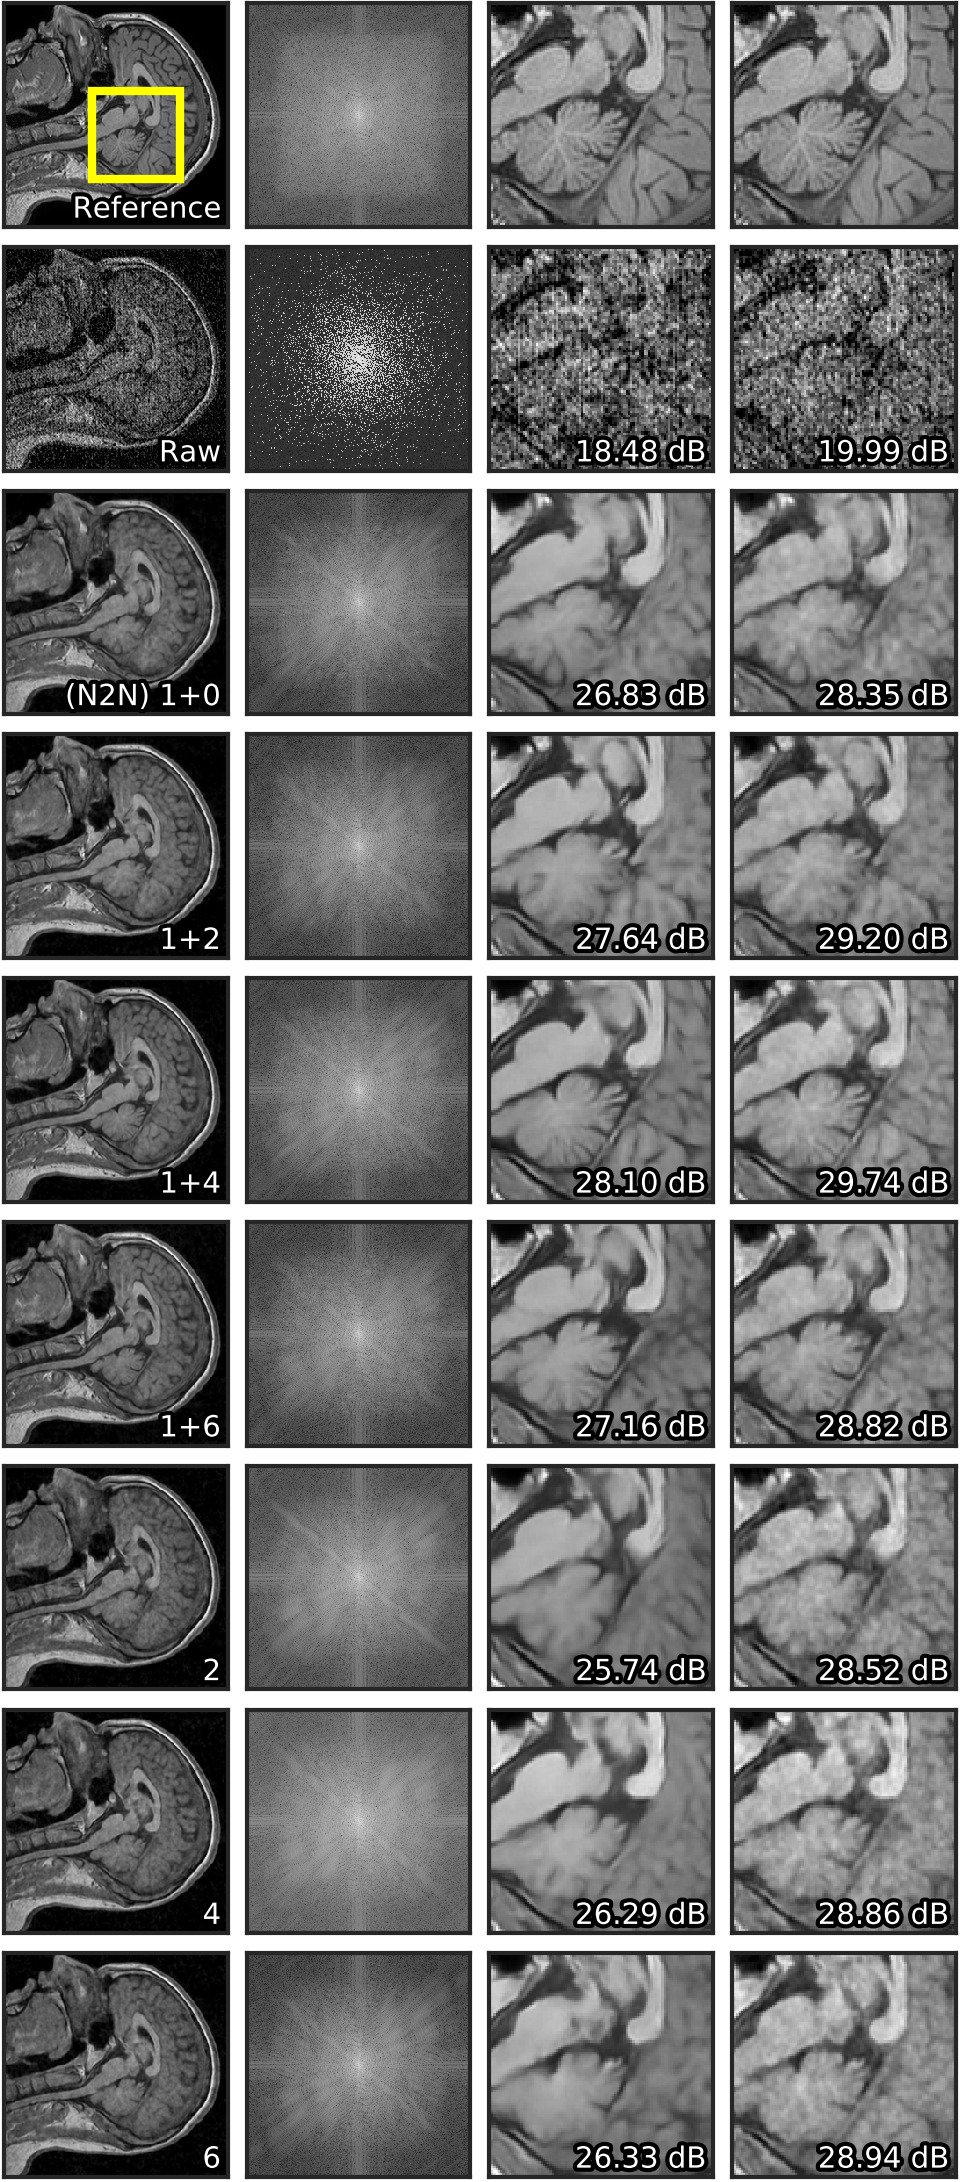

| a) Image | b) Spectrum | c) Crop | d) Crop (PP) |